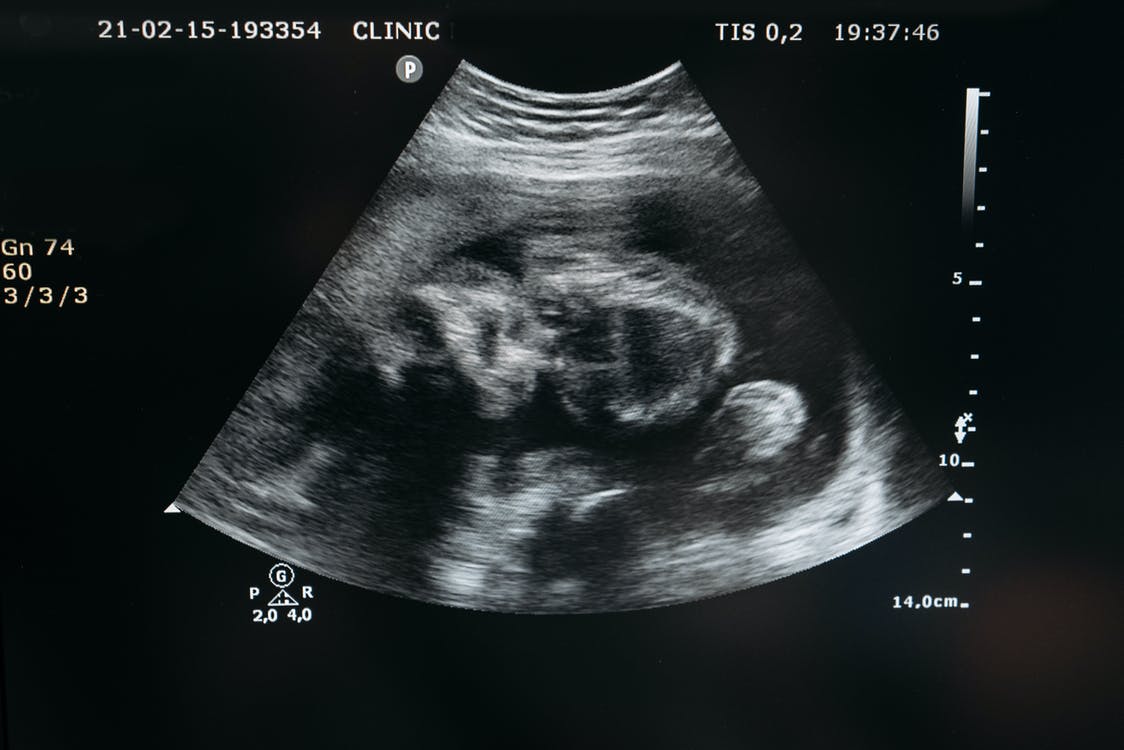

Fig1.1 SCP-CN-2414的胎儿,摄于2021年2月15日。

描述:SCP-CN-2414是一名处于早期妊娠状态的女性,处女膜完整,年龄在18至22岁之间。

初次发现时,SCP-CN-2414被置于Site-240标准人形收容单间#02721的病床上,并处于昏迷状态,无注射或流质饮食痕迹,且穿着红色和紫色的丝绸袍子。自1996年6月10日有记录被基金会实施收容以来,SCP-CN-2414的外貌未发生任何变化,身体不生褥疮且无衰老迹象。根据初次收容时的调查,确信对SCP-CN-2414的收容历史早于其发现时间,但无任何记录和人员指明SCP-CN-2414的来源和具体异常性质。